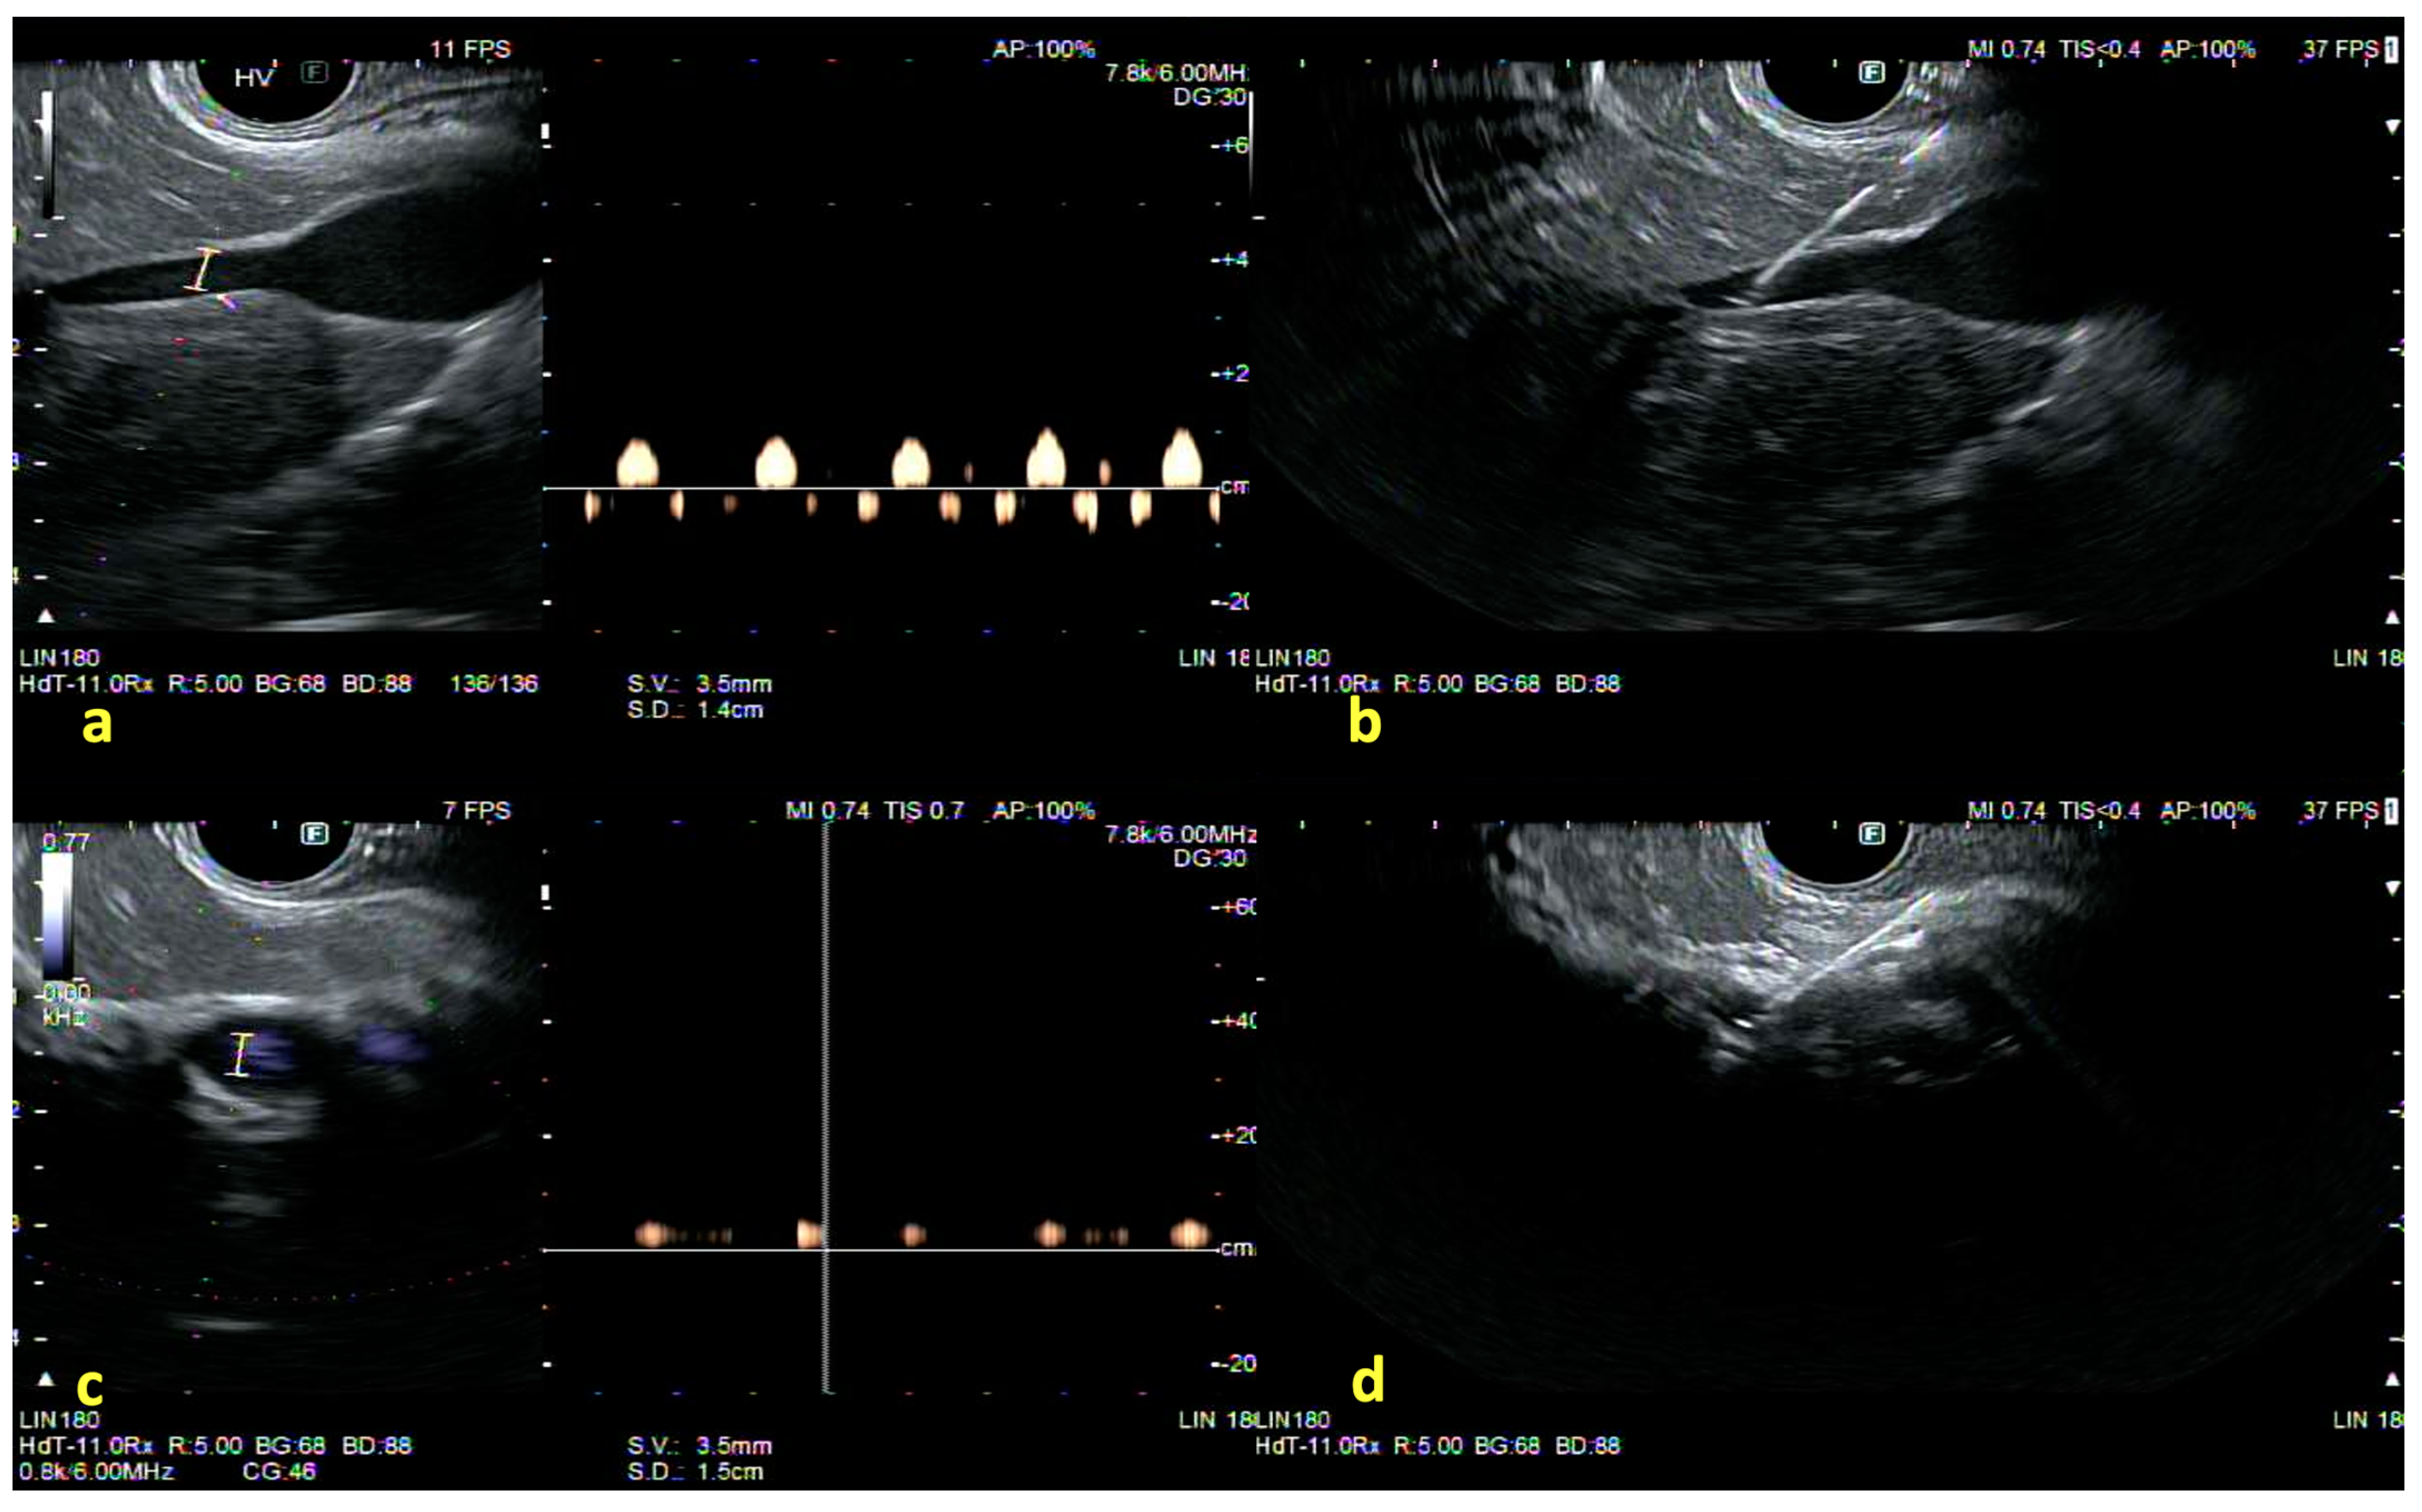

5. Portal Pressure Gradient Measurement